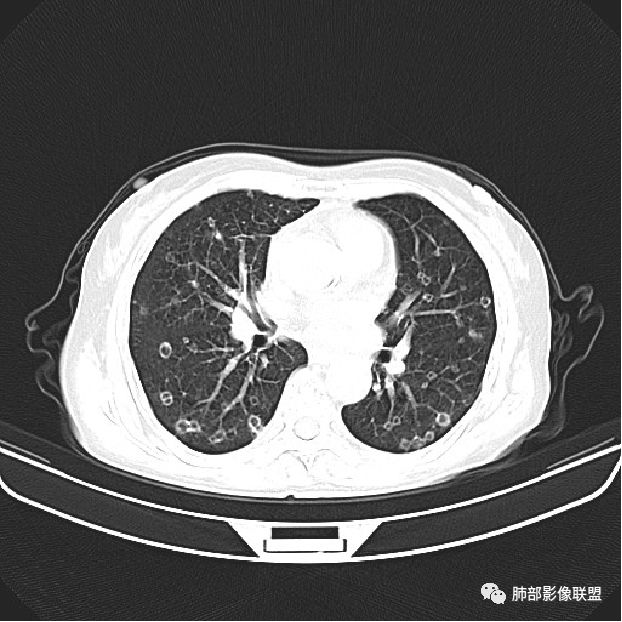

背景是慢阻肺背景。病灶是多发结节伴空洞,内部见结节影,即空洞内结节,符合得有:GPA,癌,结核,真菌(隐球菌,曲霉)

所有结节都类似;有的超不像ca

肺是发生转移瘤最多的脏器,几乎所有恶性肿瘤都可转移到肺,血行转移是最重要的转移途径。典型的肺转移瘤表现为多发圆形、大小不一的实性结节,边缘一般光整,多位于肺周边,多能明确诊断。空洞型肺转移瘤相对少见,约占肺转移瘤4%,其中70%为鳞癌转移;常见的空洞型肺转移瘤的原发恶性肿瘤多见于头颈部的鳞状上皮癌、胃肠道的腺癌和女性的生殖系统肿瘤以及其他部位的肉瘤等,组织学以鳞癌和腺癌最多见。

其中囊样空洞和小环形空洞属于薄壁空洞,泡样空洞和不规则空洞属于厚壁空洞,其中腺癌空洞型肺转移瘤主要表现为小环形空洞,以下3个病例均表现为小环形空洞的转移瘤:

肺腺癌伴双肺转移,双肺多发环形薄壁囊腔转移瘤;

颈部淋巴结病检:腺癌;双肺多发薄壁囊腔性转移瘤;

病史为结肠腺癌;双肺多发薄壁囊腔转移瘤

本病例左肺下叶肿块,有深分叶、毛刺、胸膜牵拉凹陷、支气管截断及纵隔内淋巴结肿大等征象,都均支持病灶为恶性,如腺癌,而且叶间裂的多发结节也提示是腺癌来源可能大;双肺多发结节、肿块,大部分病灶有分叶、毛刺及胸膜凹陷的恶性征象,与原发肿瘤本身的性质有关,所以应该与左肺下叶肿块同源,而且双肺多发病灶内空洞也具有多样性;

此病例中空洞形态多样,内壁不光整,有分隔影,周围未见明显卫星灶及钙化灶,结核不太符合;患者病史慢性病史,无明显发热,缺乏中毒临床表现,急性感染基本排除;各种中性粒细胞胞浆抗体阴性,没有鼻窦炎,肾脏等病史,基本排除血管炎;霉菌性空洞常见于免疫机能低下者, 常为空洞、肺炎、伴“ 晕圈”征的结节及支气管扩张合并存在。